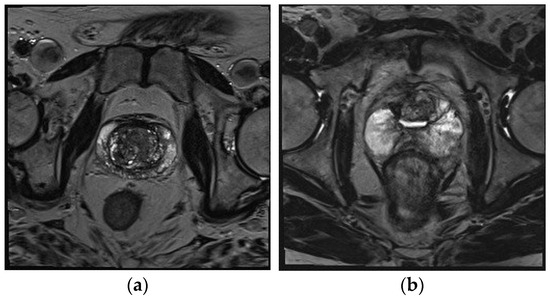

A dataset of PCa MRI images, publicly available to researchers via the Kaggle platform, was used in this study. The dataset consists of a total of 620 prostate MRI images divided into two classes: 240 ‘benign’ and 380 ‘malignant’. Each MRI image in the dataset is black and white, with an 8-bit depth, a resolution of 96 dpi, and in JPG format. The images in the benign class have a resolution of 320 × 320 pixels, while those in the malignant class have a resolution of 256 × 256 pixels. A sample image from each class in the dataset is shown in Figure 1.

Figure 1. MRI image samples of PCa dataset: (a) benign and (b) malignant.